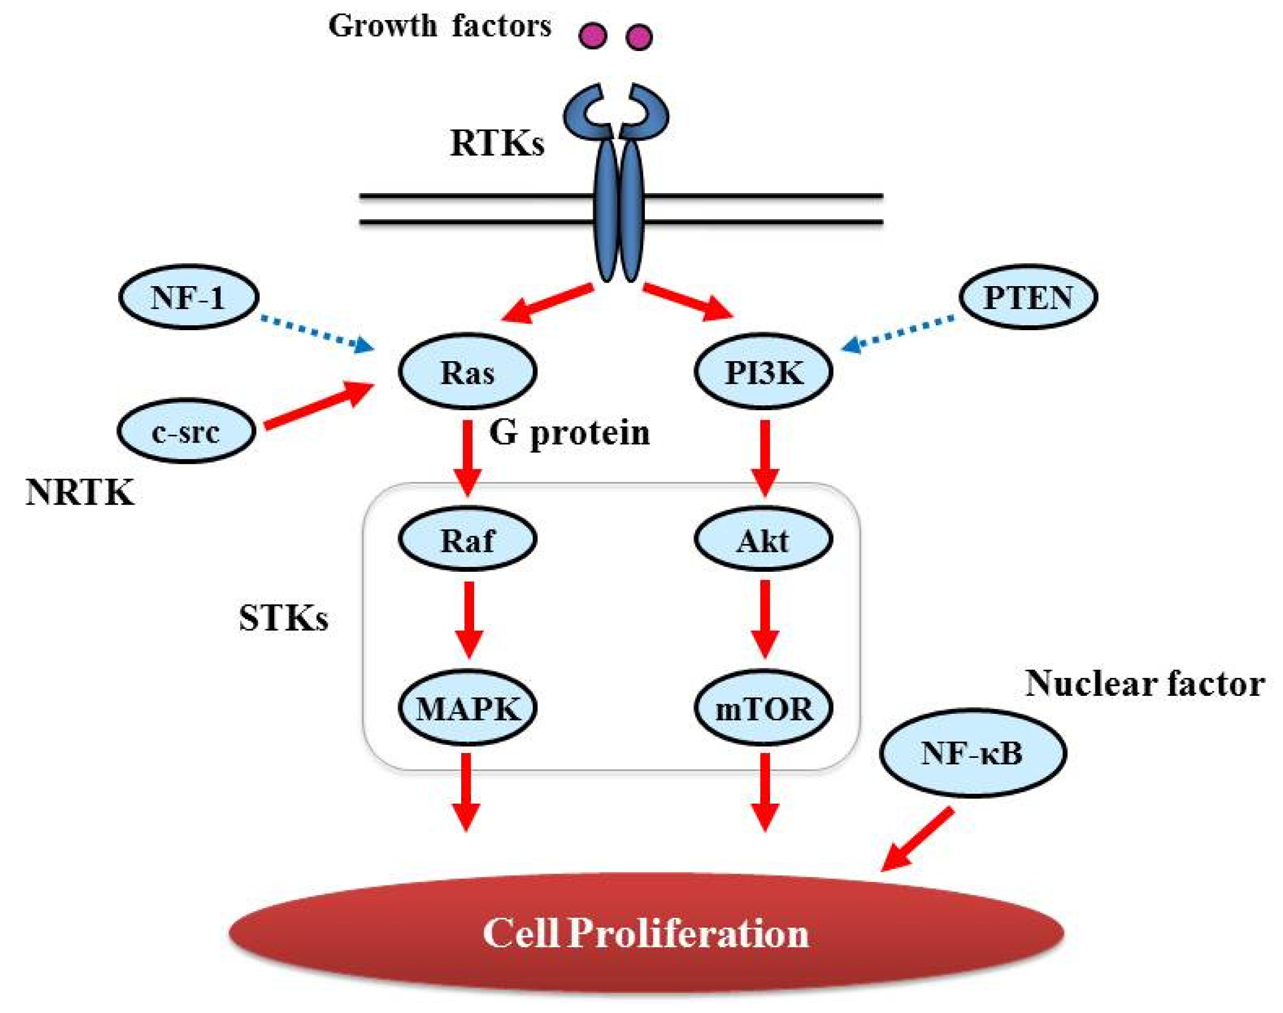

Proliferative activity with histopathologically detectable mitoses is prominent in almost all GBM cases. It is essential to define the contribution of proliferation signaling (or growth factor-mediated signaling) to the GBM cellular phenotype in order to understand the biology of transformation in the CNS. Two of the most important signaling cascades frequently deregulated in glioma are the PI3K/Akt/mTOR and Ras/MEK/MAPK pathways (Figure 3).

3.2.1. GTPase activating protein (G protein)

Ras genes, an abbreviation of Rat Sarcoma, encode a protein family of small GTPases that cycle between inactive GDP-bound and active GTP-bound conformations by coupling cell membrane growth factor receptors such as EGFR; they regulate cellular signal transduction by acting as a one-way switch for the transmission of extracellular growth signals to the nucleus [41]. Because these signals result in cell growth and division, dysregulated Ras signaling can lead to oncogenesis and cancer [42]. Ras activates a number of signaling pathways that include stem cell factor (SCF)/c-kit signaling, mammalian target of rapamycin (mTOR), and mitogen-activated protein (MAP) kinases pathways. The role of Ras in GBM is described in detail in “Major signaling and related molecules”.

3.2.2. Serine/threonine specific protein kinase (STK)

The protein kinase family of enzymes plays a pivotal role in signal transduction across the cell membrane as well as inside cells [43]. Both types of protein kinases, TK and STK, share a high sequence similarity in their catalytic domains, which suggests that they descended from a common ancestral gene. STK have received comparatively little attention, vis-a-vis TKs, in terms of their involvement in cancers [44]. In contrast to the TKs, most of the known STKs are cytoplasmic proteins.

STK belongs to the family of transferases, specifically those that transfer phosphorus-containing groups as protein-serine/threonine kinases. STK expression is altered in various cancers. Akt is one of the STKs that play a key role in cellular proliferation. GBM frequently contains alterations in PTEN (Phosphatase and Tensin Homolog Deleted from Chromosome 10) [45] that is a lipid phosphatase and lead to activation of the Akt/mTOR pathway [46]. BRAF, v-RAF murine sarcoma viral oncogene homolog B1, is also an STK and a member of the RAS/RAF/MEK (MAPK kinase)/MAPK pathway that is commonly activated by somatic point mutation V600E in pilocytic astrocytoma [47]. In contrast, this mutation is rarely reported in GBM [48].

3.2.3. Nuclear Factor

NF-κB, nuclear factor kappa-light-chain-enhancer of activated B cells, is a protein complex that controls DNA transcription and regulates genes that control cell proliferation and cell survival [51]. Aberrant constitutive activation of NF-κB in GBM in response to PDGF overexpression promotes glioma cell proliferation [51]. The PI3K pathway has been implicated in mediating the activation of NF-κB by PDGF, and inactivation of PTEN and PDGF expression may contribute to the high levels of NF-κB [52].